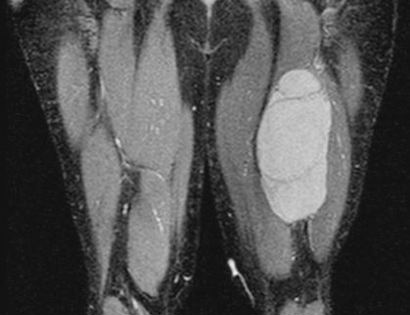

MRI of hamstrings tumor

This is an MRI of the hamstrings tumor. The tumor is the brightened part on the right hand side of the thigh in the image seen.